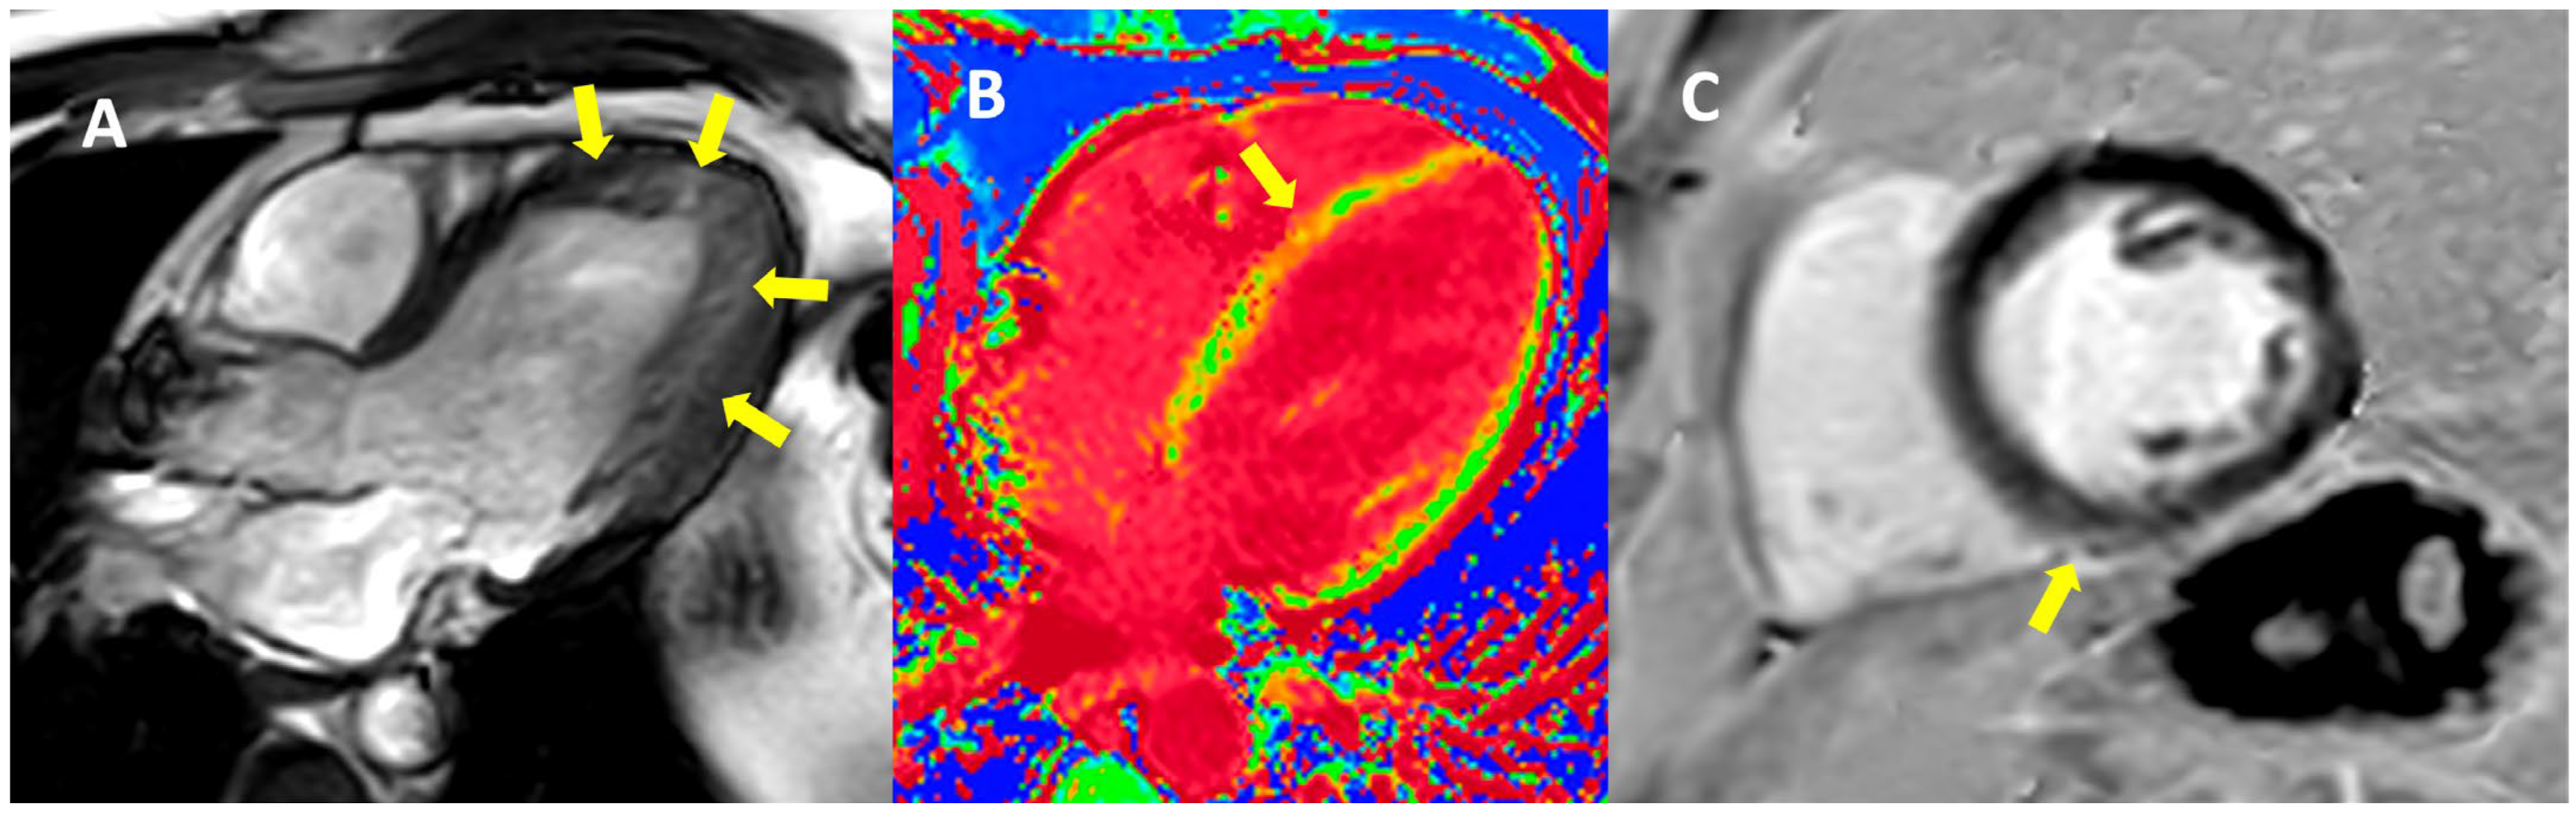

| Echocardiography | Hypokinetic non-dilated cardiomyopathy LVEF = 42% Mild mitral regurgitation IAS aneurysm | Hypokinetic non-dilated cardiomyopathy LVEF = 34% Mild mitral regurgitation IAS aneurysm | Left ventricular concentric hypertrophy LVEF = 54% |

| Cardiac magnetic resonance imaging | Hypokinetic non-dilated cardiomyopathy Left ventricular non-compaction LVEF = 50% | Hypokinetic non-dilated cardiomyopathy Regional sub-epicardial fibrosis LVEF = 41% | Not carried out |